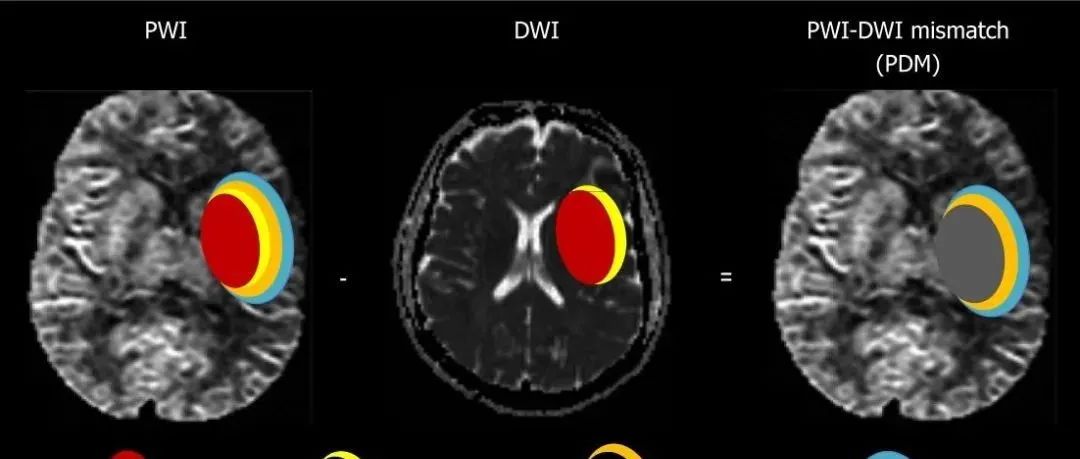

神经指南:急性脑梗死缺血半暗带临床评估和治疗中国专家共识

导读脑梗死急性期以血管再通为核心的各种治疗措施,主要是挽救梗死灶周围因缺血性损伤而发生功能异常、但尚未死亡的神经细胞,使其恢复正常并促进神经功能恢复。梗死灶周围这种仍有救治机会的神经组织,一般被认为属于“缺血半暗带(ischemic penumbra)”。缺血半暗带已成为急性脑梗死的关注焦点,其临床评估和治疗受到血管神经病学和相关学科医生的高度重视。然而,目前国内外对急性脑梗死缺血半暗带的临床评估和判定标准并不一致,治疗亦未形成共识。在中国医师协会神经内科医师分会领导下,由脑血管病专委会(学组)组织我国相关领域专家,经全面复习国内外文献,反复讨论后撰写成以下共识,供国内同行在临床实践中评估和治疗急性脑梗死缺血半暗带时参考。...